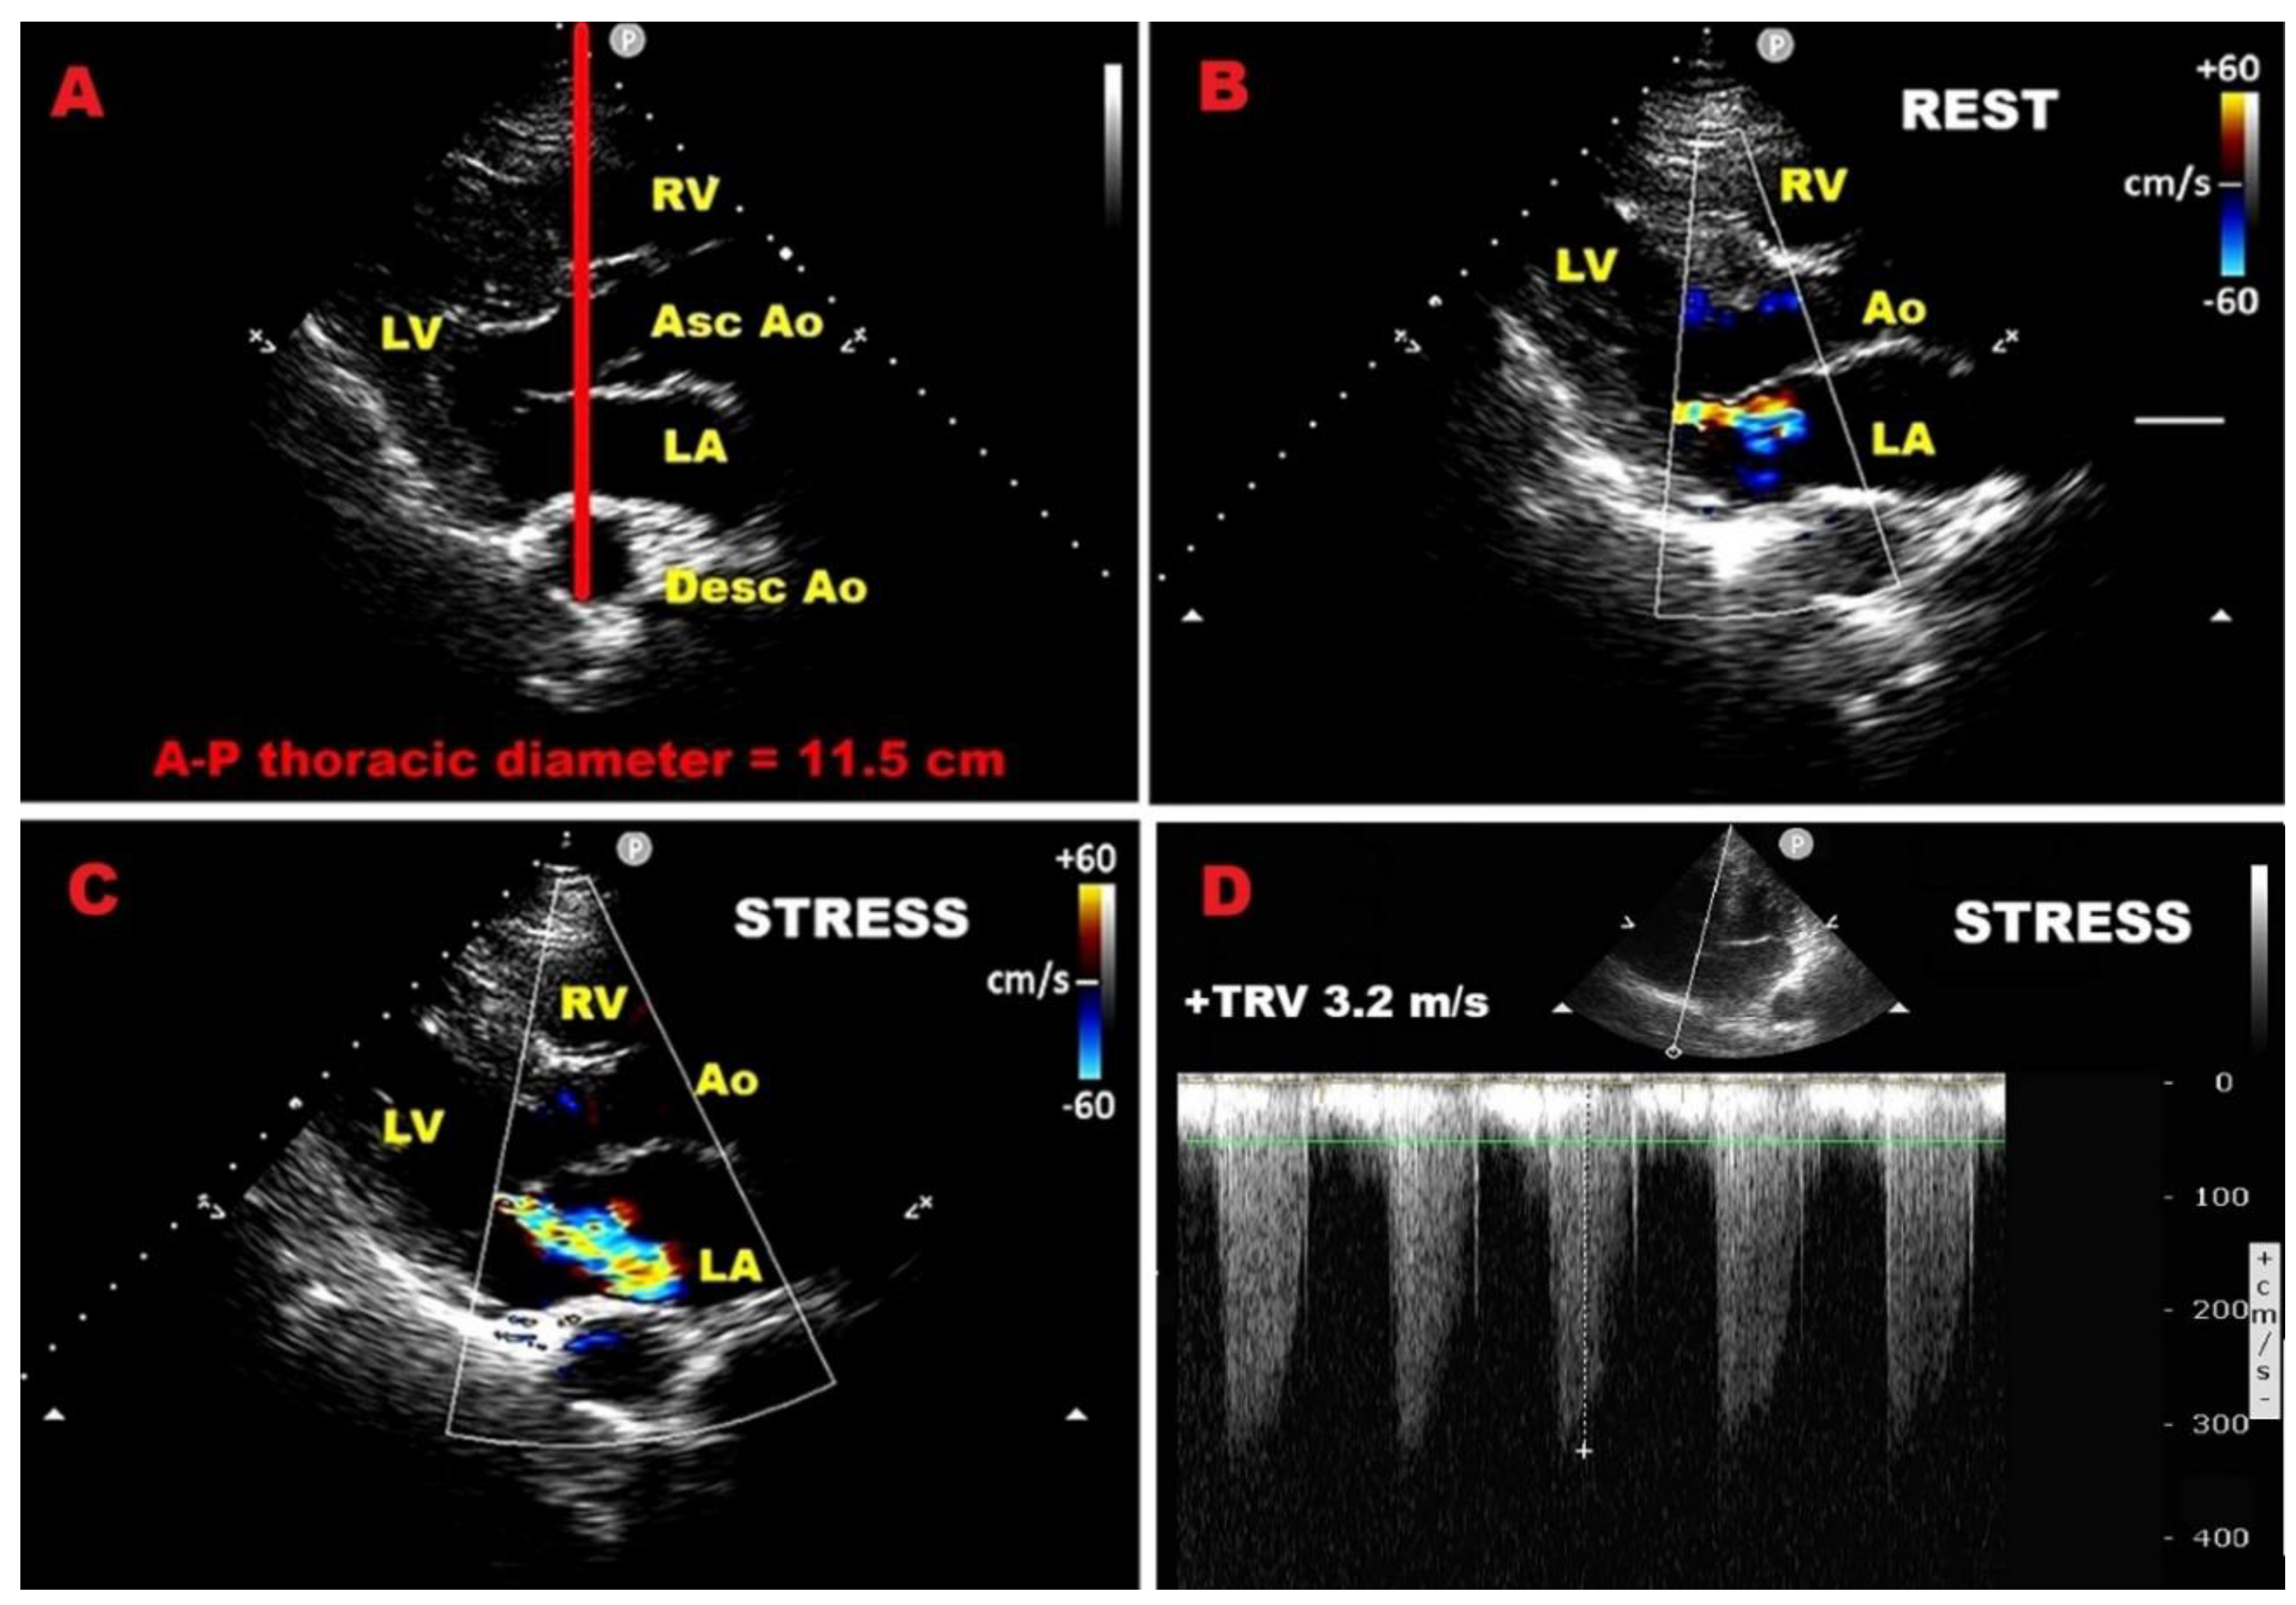

4.1. Exercise stress echocardiography

7.4. Influence of chest wall conformation on ESE results

| Category | Prognostic Indicator | Threshold / Definition | Clinical Implication |

| LV systolic function | Exercise LVEF | < 68% | Predicts postoperative LV dysfunction |

| LVESVi | ≥ 25 mL/m² | Predicts postoperative LV dysfunction | |

| LV–GLS normalized for LVESD | Worse than –5.7%/cm | Predicts postoperative LV dysfunction | |

| Contractile reserve (LVEF) | Δ ≥ 4% | Protective; absence predicts adverse outcomes | |

| Contractile reserve (LV–GLS) |

Δ ≥ 1.9% | Protective; absence predicts adverse outcomes | |

| Blunted GLS increase | < 2% during exercise | Identifies early subclinical dysfunction | |

| Mitral regurgitation dynamics | Increase in EROA | Δ ≥ 10 mm² | Predicts adverse CV outcomes |

| Increase in regurgitant volume | Δ ≥ 10 mL | Predicts adverse CV outcomes | |

| Dynamic MR | MR worsens to severe during exercise | Linked with worse prognosis | |

| Pulmonary pressures | Exercise sPAP | > 60 mmHg | Predicts symptom onset & adverse outcomes |

| Right ventricular function | Exercise TAPSE | ≤ 18 mm (high-risk) | Associated with poor prognosis & CV events |

| Diastolic stress echo | Septal E/e′ | > 15 (abnormal) | Indicates elevated filling pressures |

| Average E/e′ | > 14 (abnormal) | Indicates elevated filling pressures | |

| TRV | > 2.8 m/s | Indicates exercise-induced PH | |

| Normal response | Septal E/e′ < 10 and TRV < 2.8 m/s |

Favourable prognosis |